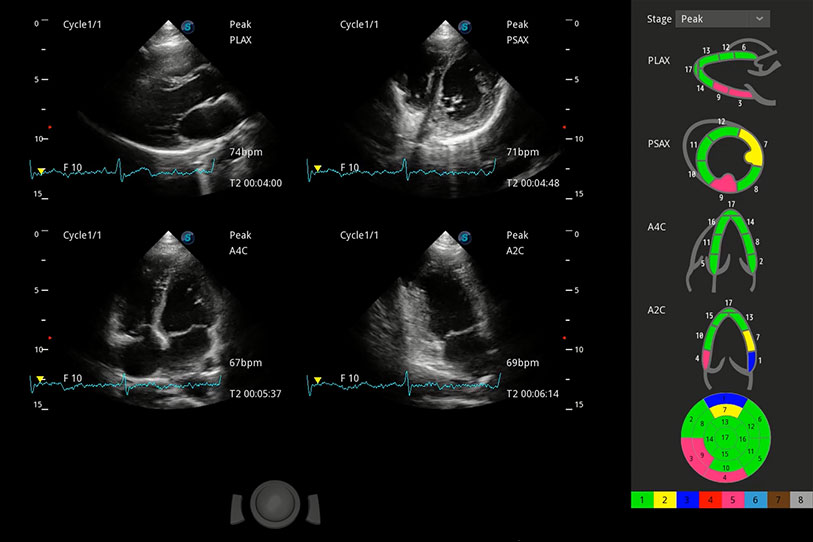

能夠基于左心室壁追蹤和辛普森法,自動計(jì)算射血分?jǐn)?shù),支持多個可移動點(diǎn)描跡,與手動測量相比,極大節(jié)省了動物醫(yī)生的時間和精力。

具備多種協(xié)議可選,同時支持17階段劃分法和專業(yè)的SE報(bào)告。

通過360度任意調(diào)節(jié)3條M型取樣線,在同一心動周期上觀察心臟不同位置的運(yùn)動曲線,得到準(zhǔn)確的心功能測量數(shù)據(jù),有效評估心肌運(yùn)動及左心室功能。

實(shí)時用顏色表示心肌組織運(yùn)動,觀察和定量組織的運(yùn)動情況,對快速檢測與評估心肌的灌注和活性、電傳導(dǎo)及心肌收縮和舒張功能等均能提供重要的診斷信息。